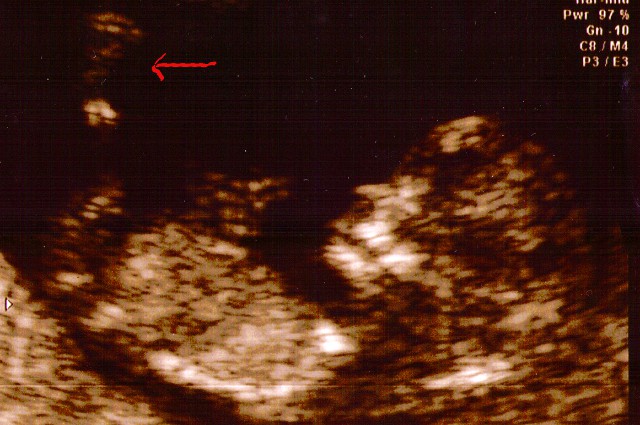

And here you are now, just a month later, with two arms, two legs and even a brain (that last one is important, hold on to it if you can).

I think you have your mother's nose. She thinks you have mine. We'll see in about six months (the arrow points to your leg, not your nose).